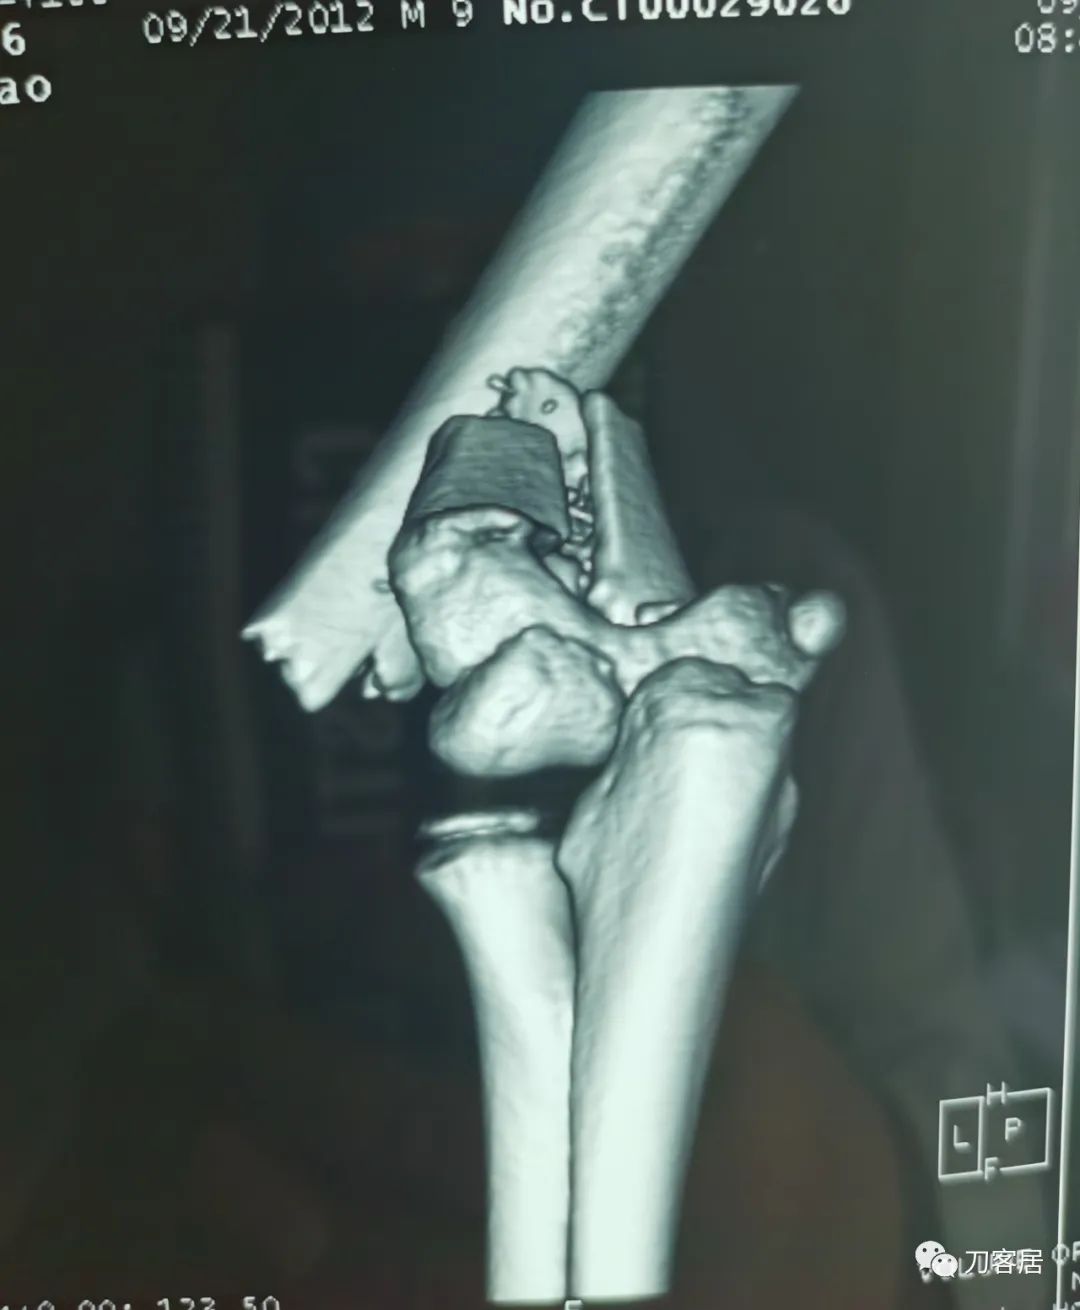

查体:左侧肘关节肿胀明显、疼痛、畸形,局部可见明显青紫瘀斑,左肘关节活动受限,肱骨远端环形压痛(+),局部可及异常活动及骨擦感形成,左上肢末梢桡动脉可触及,左侧腕关节及拇指背伸活动受限,左侧虎口区感觉麻木。辅助检查:自带X线及CT片示:左肱骨髁间粉碎性骨折。

入院诊断:1. 左肱骨髁间粉碎性骨折;2.左肱骨远端骨骺损伤;3. 左桡神经损伤。

20210922当地省中医院三维CT03